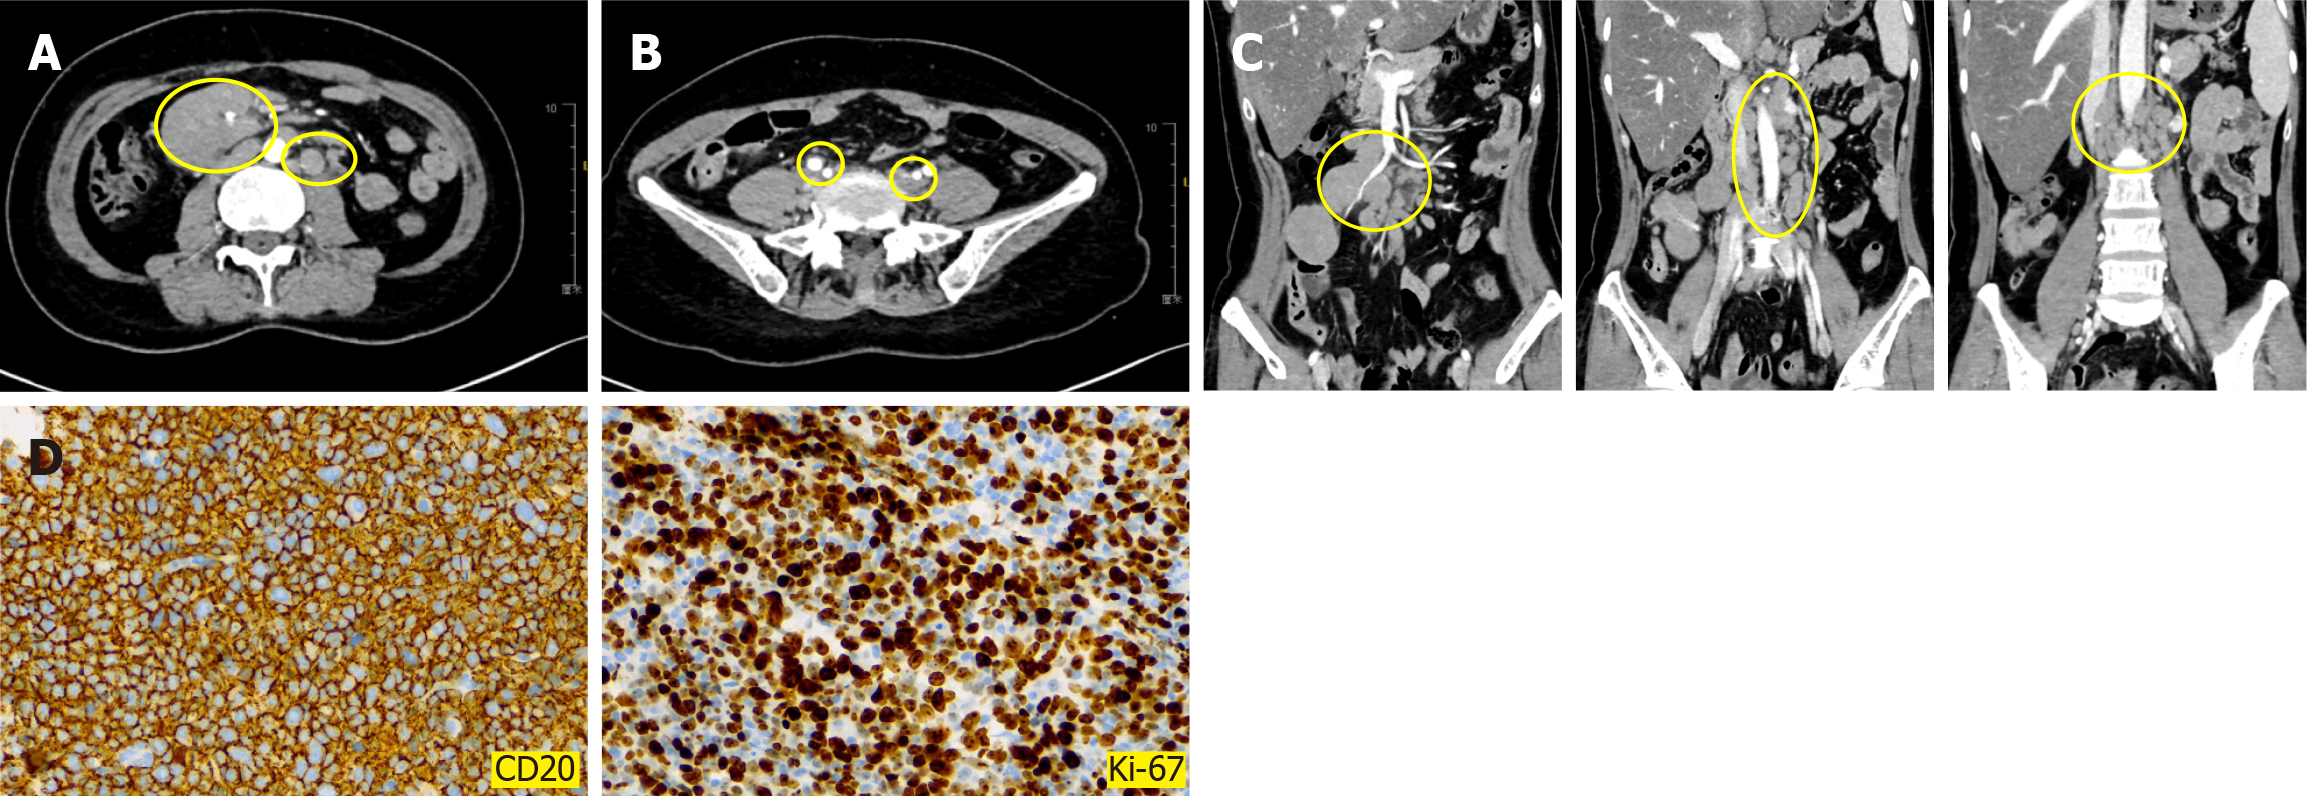

Immunological examination: In November 2017, rotational resection of a breast mass was performed. Immunohistochemistry revealed CK5/6 (-), P63 (-), CD10 (-), E-cadherin (+), P120 (membrane+), ER (90%), PR (5%), HER-2 (0), P53 (+), P16 (-), epidermal growth factor receptor (-), and Ki-67 (60%) (Figure 1A). These tests suggested a diagnosis of invasive ductal carcinoma of the breast. Routine blood test, urinalysis, routine stool and liver and kidney function did not find any significant abnormalities.

Breast ultrasound revealed a solid mass in the left breast (BI-RADS 4b grade) with a diameter of 2.4 cm and lymph node ultrasound identified oval hypoechoic mass in the bilateral (Figure 1B). Abdominal ultrasound and chest computed tomo

In August 2023, re-examination CT identified multiple enlarged lymph nodes in the abdominal cavity (Figure 2A-C). Subsequently, the pathological biopsy of the right abdominal mass was performed and immunohistochemical examina

A final diagnosis of metachronous MPC was made, with invasive ductal carcinoma of the breast (T3N1M0 stage IIIA LuminalB type) as the first primary cancer and DLBCL (stage IIIA) as the second primary cancer.

Currently, the diagnosis of MPC is challenging, especially for patients with solid tumors as the first primary cancer and hematological or lymphatic system tumors as the second primary cancer. This is because patients present with symptoms such as high fever and lymph node enlargement, requiring that clinicians distinguish them from the recurrence of the first primary cancer or other febrile diseases. In this report, the patient was diagnosed with invasive breast cancer during physical examination and she underwent a modified radical mastectomy to treat the left breast cancer. Notably, the patient did not manifest any symptoms before the identification of NHL. A follow-up PET-CT examination performed five years and nine months after surgery revealed multiple soft tissue nodules in the abdominal aorta and right lower abdominal cavity, with mildly increased glucose metabolism and a PET-CT standard uptake value of 2.0, suggesting a high possibility of hematological disease. Lymph node pathological examination confirmed a diagnosis of DLBCL.